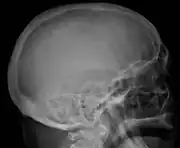

The diagnostic examination of a person with suspected multiple myeloma typically includes a skeletal survey. This is a series of X-rays of the skull, axial skeleton, and proximal long bones. Myeloma activity sometimes appears as "lytic lesions" (with local disappearance of normal bone due to resorption) or as "punched-out lesions" on the skull X-ray ("raindrop skull"). Lesions may also be sclerotic, which is seen as radiodense.[76] Overall, the radiodensity of myeloma is between −30 and 120 Hounsfield units (HU).[77] Magnetic resonance imaging is more sensitive than simple X-rays in the detection of lytic lesions, and may supersede a skeletal survey, especially when vertebral disease is suspected. Occasionally, a CT scan is performed to measure the size of soft-tissue plasmacytomas. Nuclear Medicine Bone scans are typically not of any additional value in the workup of people with myeloma (no new bone formation; lytic lesions not well visualized on nuclear bone scan).

Skull X-ray showing multiple lucencies due to multiple myeloma